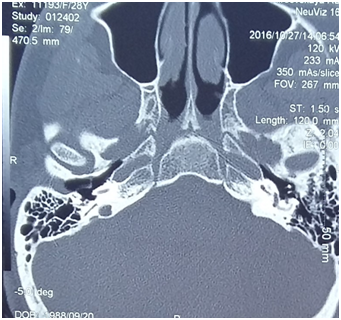

Computed tomography (CT) with contrast (Ultravist 370, 100 ml) was performed (Figure 1). Significant dilatation of right foramen jugularis with its right side destruction was detected: the left one size was 8x7 mm, the right one was 12x14.6 mm. In fossa jugularis we revealed a soft tissue mass with clear contours, homogeneous, destroying right wall of foramen jugularis. Enhanced-CT examination showed a significant enhancing mass. The radiological findings were consistent with those of a jugular paraganglioma.1

Figure 1 Results of computed tomography of the brain with contrast (Ultravist 370, 100 ml).